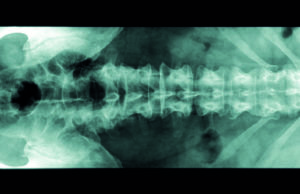

Study: Lumbar spine stabilization surgery may be a risk factor in...

Lumbar spine stabilization surgery may be a risk factor in the development of symptomatic venous outflow obstruction lesions, a study published in the Journal...